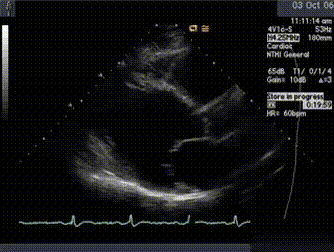

The best test to look into someone’s heart and identify the problem accurately in children and adults both.